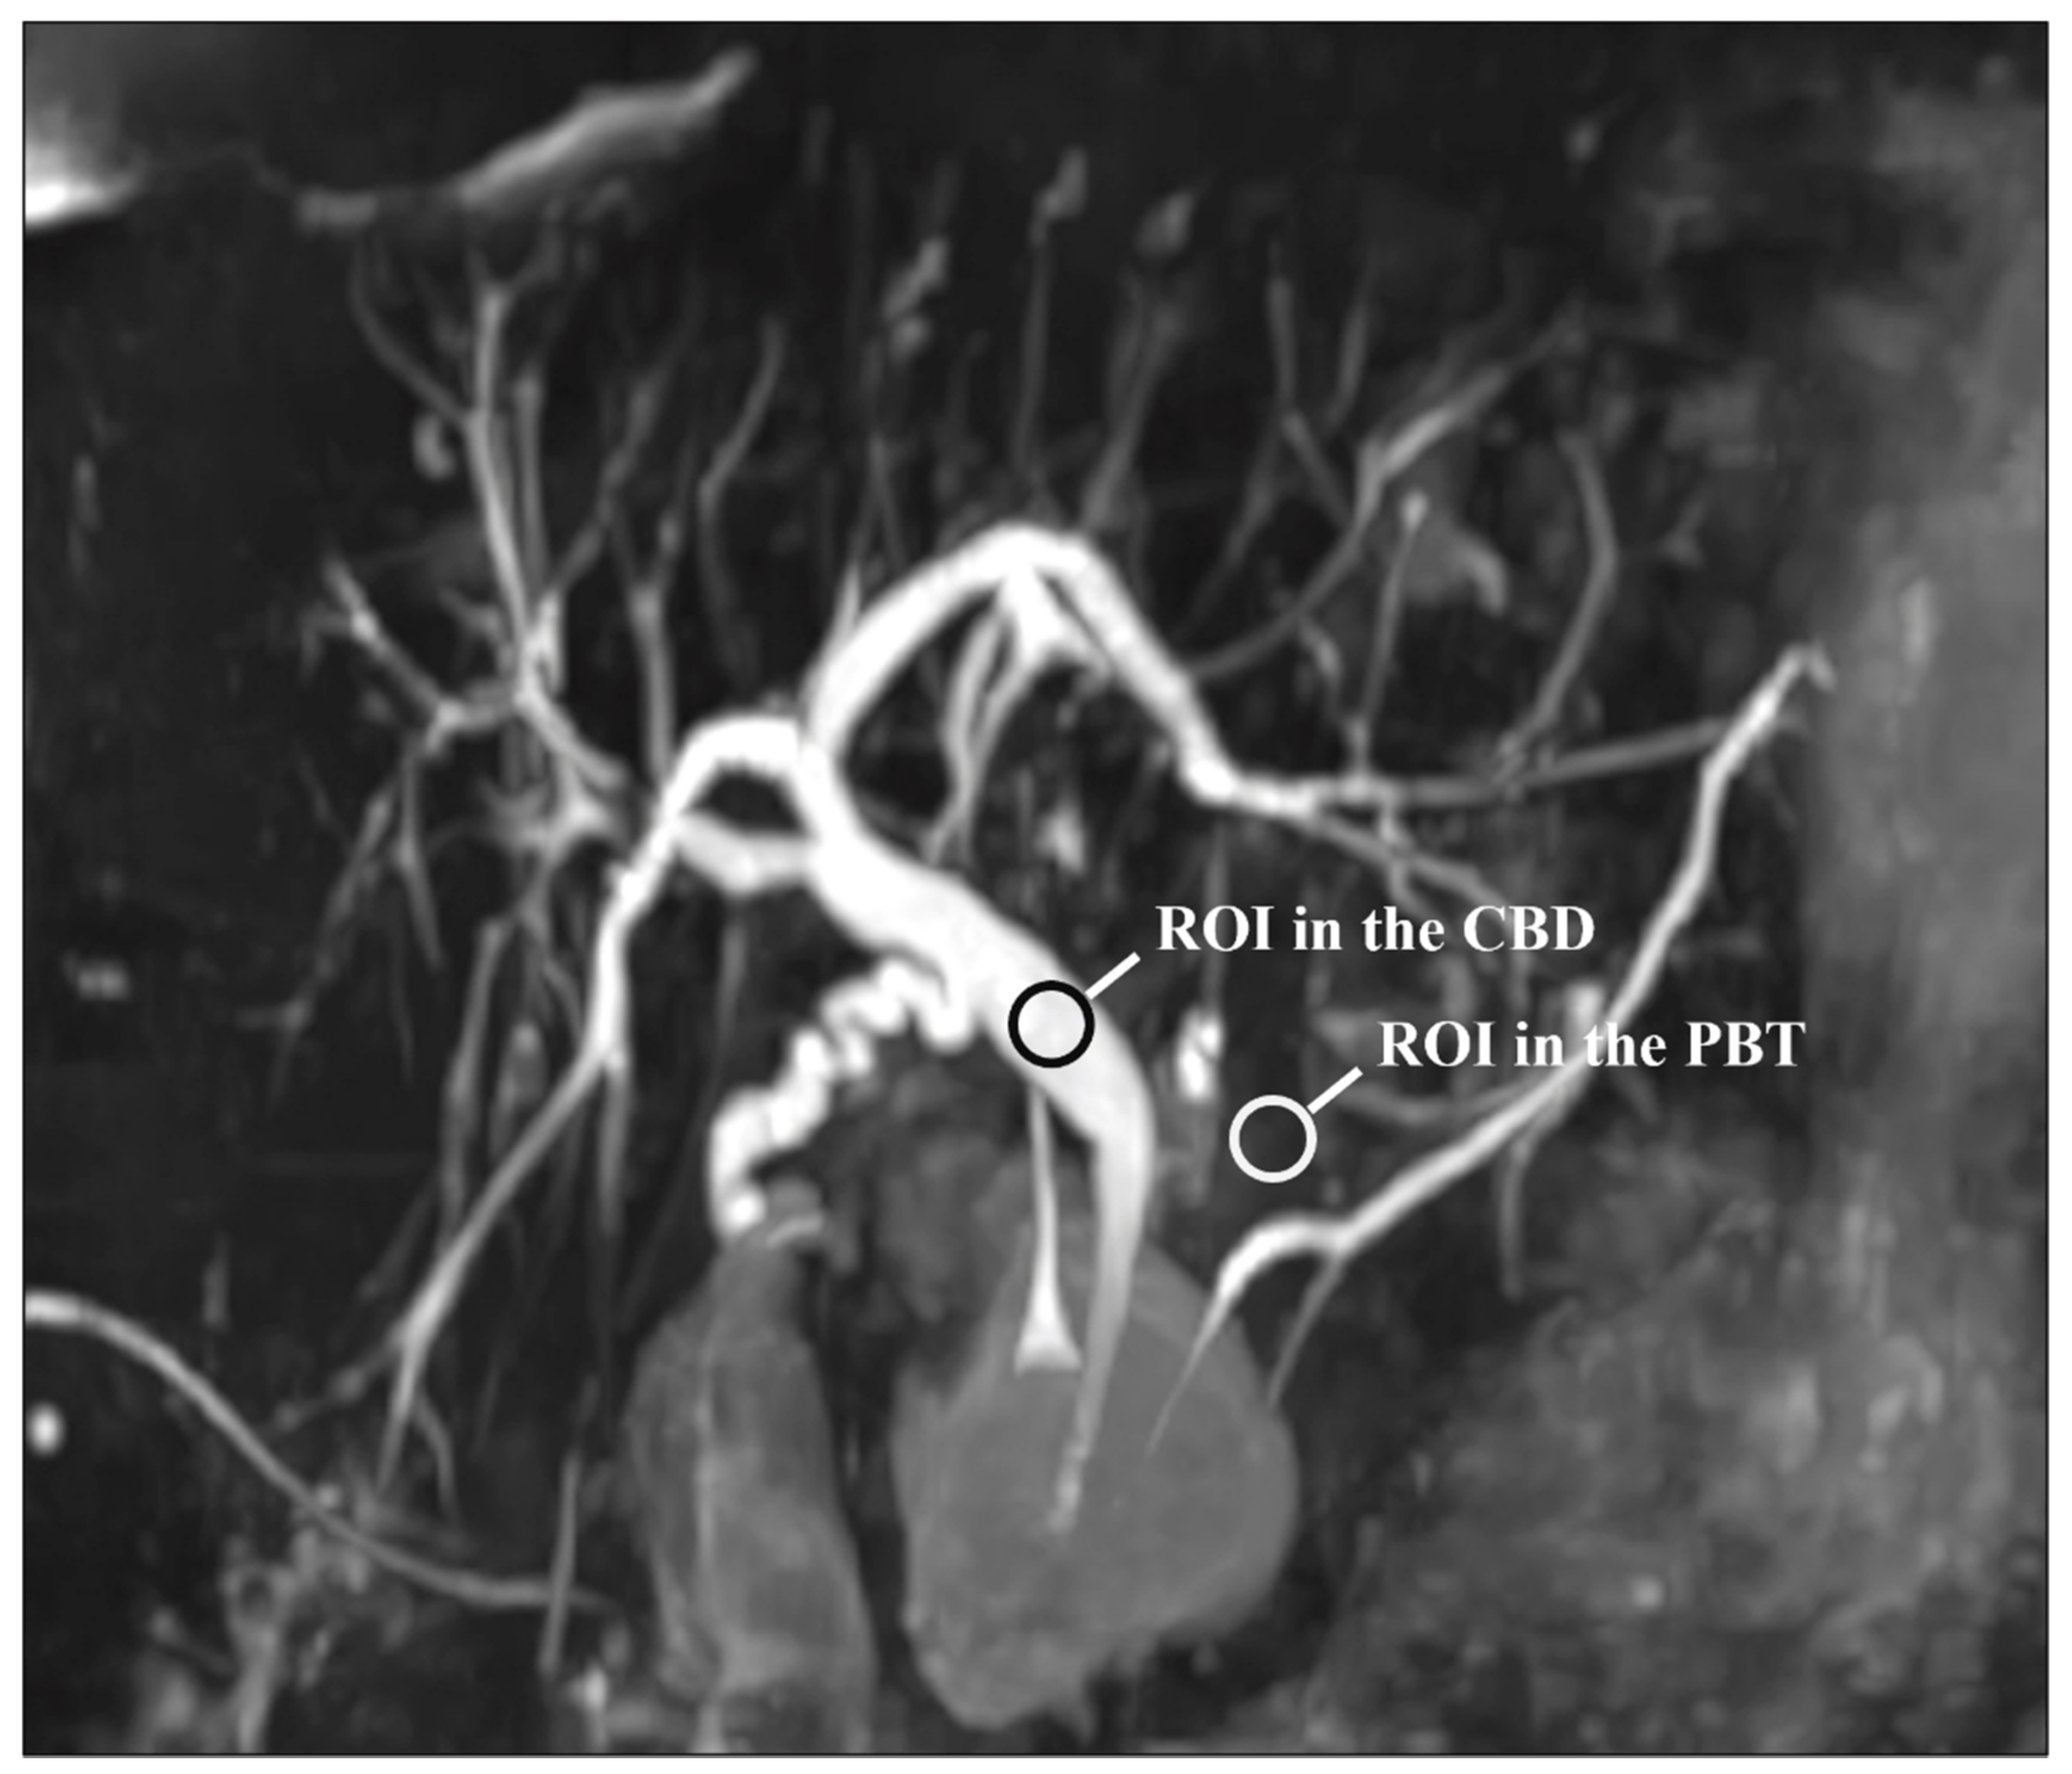

For each patient and each sequence, a representative section of the CBD was selected. Then, circular regions of interest (ROIs) were traced on the CBD and PBT and the mean signal intensities were recorded. The CBD ROI was at least 5 mm² and was placed in a uniform artifact-free region in the middle of the duct. A similar ROI was positioned on the peri-CBD tissues, avoiding artifacts and fluid-containing structures. Note that the ROIs were drawn on the native images. Figure 1 shows the ROIs placement. The CR was estimated using the following formula [23,29,30]:

Figure 1. Representative section of the common bile duct (CBD) used for the quantitative evaluation of image quality: note the regions of interest (ROIs) on the CBD and peri-biliary tissues (PBT). Note that the ROIs were drawn on the native images and not on the MIP reconstruction as shown here.